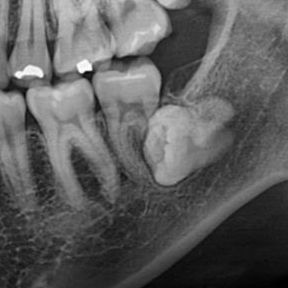

사진과 같이 매복 사랑니 때문에 앞 어금니 뿌리가 먹혔다는 진단을 받아서 둘 다 한꺼번에 발치할 예정입니다. 아무래도 임플란트를 하는 수밖에 없을까요? 혹시 다른 방법이 있을지 궁금해서 여쭤봅니다.

• 1번 째 사진

• 2번 째 사진

• 3번 째 사진